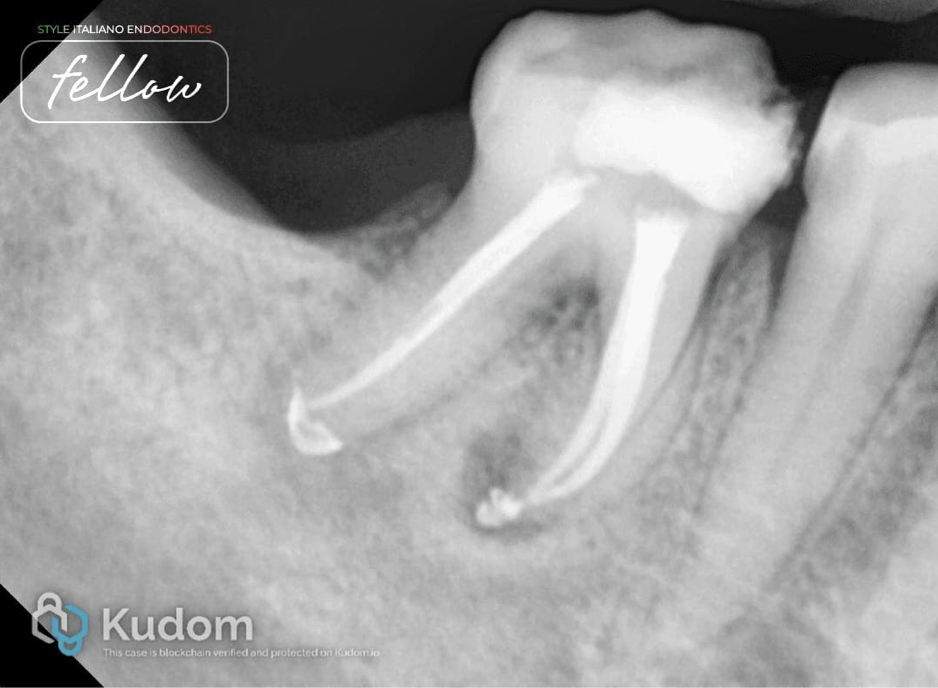

Fig. 4

After-obturation x-ray. Obturation was done with AH Plus sealer and the continuous wave of compaction method.